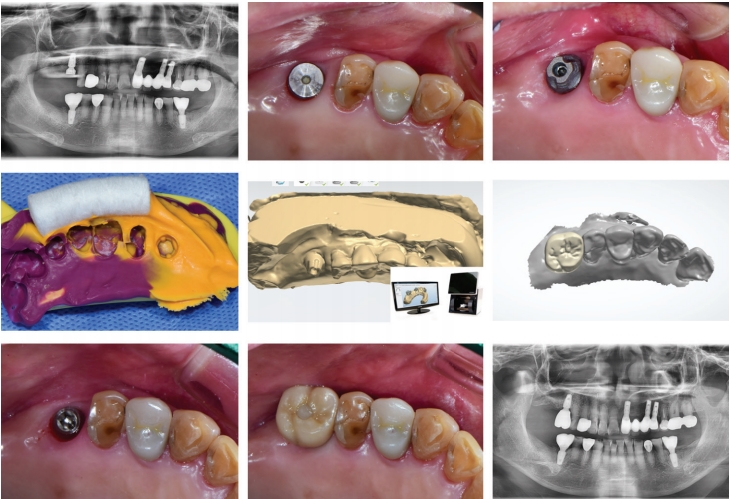

하이니스 보철시스템의 전반적인 과정을 살펴보면 다음과 같다.(Fig.1)

A. Single case (Fig. 5)

#16 bone level 임플란트에 40N으로 base abutment를 연결 후 Bite tray를 이용해 러버 인상을 채득 했다. 인상체를 기공소에서 model scanner로 디지털 전환 후 하이니스 보철 제작하였다. 진료실에 서 25N의 final torque로 보철물을 최종 delivery 했다.